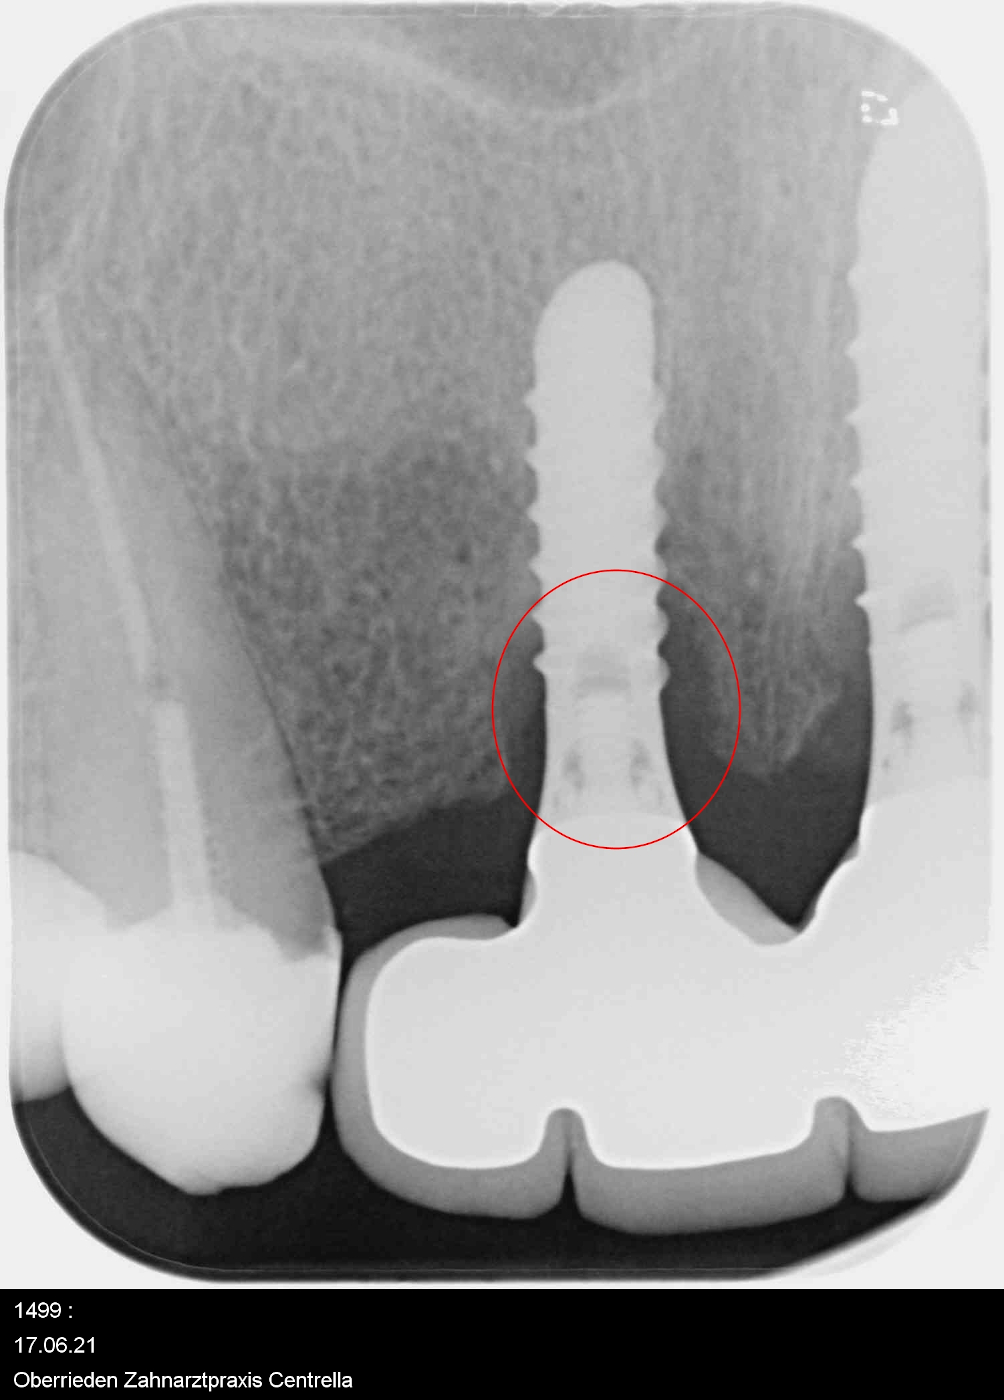

Vor der Behandlung

Unmittelbar nach der Behandlung; Knochenaufbau